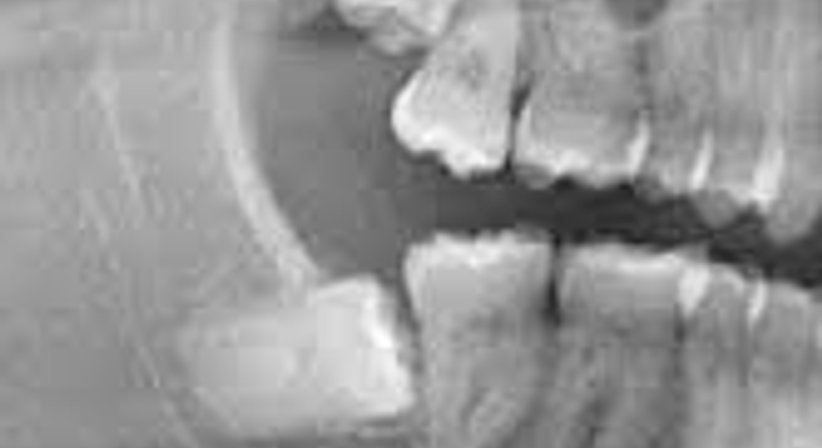

Weisheitszähne sind ein Relikt unserer Vorfahren. Im Laufe der Evolution hat sich der Kiefer beim Menschen aufgrund veränderter Nahrungsgewohnheiten verkürzt, jedoch ohne dass sich die Anzahl der Zähne verringert hätte. Deshalb finden Weisheitszähne heutzutage bei vielen Menschen nicht ausreichend Platz und brechen daher nur unvollständig oder überhaupt nicht durch. Häufig führen sie zu folgenden Beschwerden: Entzündungen (Dentitio difficilis), die sich zu Abszessen entwickeln können, Karies durch lagebedingte, schlechte Putzbarkeit und Kiefergelenksprobleme.

Bei der Operativen Weisheitszahnentfernung wird über einen Schleimhautschnitt der Weisheitszahn freigelegt, gegebenenfalls darüberliegender Knochen entfernt und der Zahn vollständig entfernt.